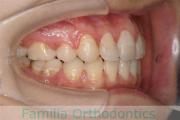

No.22V-409

- 叢生

- 16歳

- 女性

- 44

- 8|58

- FEA

- 86万円

八重歯を治したいということで来院されました。下あごの左ずれのある上顎前突(出っ歯)・叢生(でこぼこ)でしたので、上は左右から、下はで左のみ小臼歯を抜歯して、歯科矯正用アンカースクリューとマルチブラケット法にて治療を行いました。2年強、30回程度の通院が必要でした。

上下とも前歯の叢生(でこぼこ、凹凸、ガタガタ)があるため、保定を怠ると後戻りのリスクがあります。